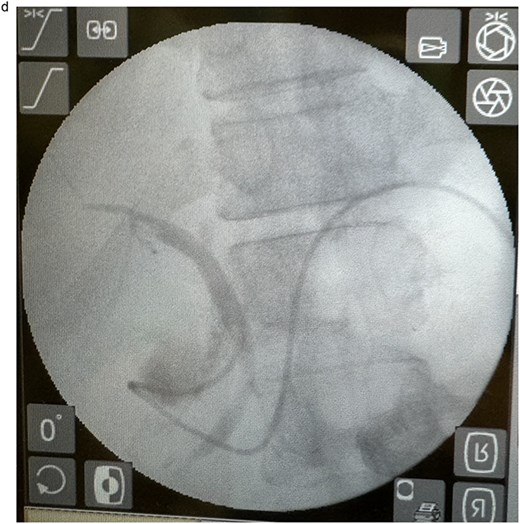

In view of the ongoing leakage and the hostile operative field, a third intervention was undertaken on postoperative day 24 following the second surgery. After multidisciplinary discussion, a combined surgical–endoscopic approach was undertaken in collaboration with internal medicine specialists. Intraoperative findings revealed dense adhesions from prior surgeries and a 0.5-cm perforation at the proximal duodenal stump, located near the ampulla of Vater. Initial endoscopic retrograde cholangiopancreatography (ERCP) was unsuccessful due to limited ampullary access; thus, EUS-CDS with ENBD placement was performed as an alternative strategy. From the duodenal bulb, the common bile duct (CBD) measured 4.7 mm on EUS, and Doppler confirmed no intervening vessels (Figs 4a and 4b). A 19-gauge EZ Shot 3 needle (Olympus) was used to puncture the extrahepatic bile duct, and bile aspiration followed by contrast injection confirmed correct positioning (Fig. 4c). A VisiGlide 2 angled guidewire (0.025 inch) was advanced into the right intrahepatic duct, and the tract was dilated using an ES dilator. A 7-Fr ENBD catheter was subsequently deployed across the choledochoduodenostomy under fluoroscopic guidance, achieving effective biliary drainage (Figs 4d and 4e). In addition, a 16-Fr Foley catheter was inserted into the duodenal perforation as a duodenostomy tube (Fig. 4f) for external drainage, and six closed wound vacuum drains were placed for peritoneal irrigation and drainage.

Schematic illustration of EUS-CDS with placement of a 7-Fr ENBD catheter into the right intrahepatic duct.

Endoscopic image demonstrating the 7-Fr ENBD catheter, with concurrent visualization of the duodenostomy tube at the proximal duodenal stump.